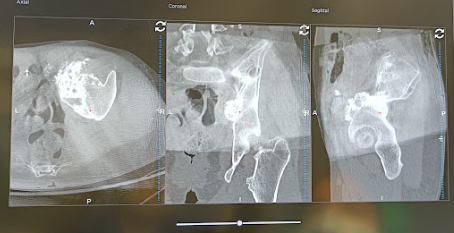

O Centro Hospitalar Universitário de Santo António realizou, recentemente, uma intervenção inédita em Portugal, a primeira cirurgia de resseção tumoral assistida por navegação computorizada.